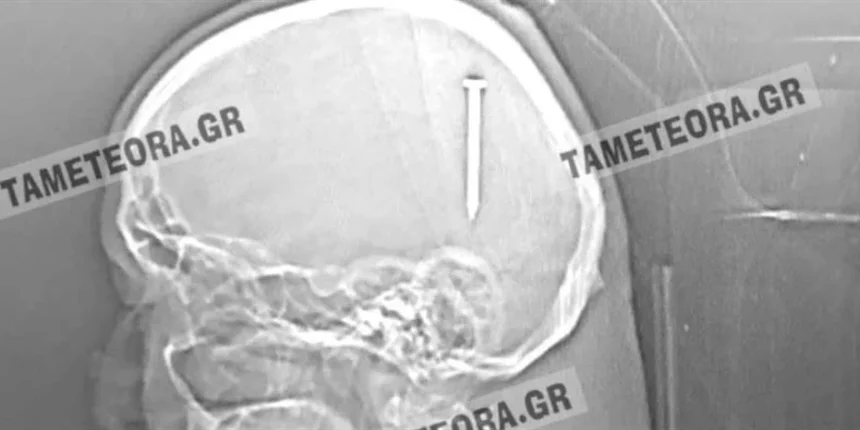

Όπως κατέγραψε η ιστοσελίδα tameteora.gr ο συμπολίτης μας βρέθηκε ξαφνικά με ένα καρφί 5 εκ. στο κεφάλι του κατά το διάστημα εργασιών που έκανε.

Εκτός από το αρχικό τράνταγμα που ένιωσε δεν ακολούθησε ούτε πόνος ούτε κάποιο άλλο σύμπτωμα.

Αρχικά μεταφέρθηκε στο Κέντρο Υγείας Καλαμπάκας, στη συνέχεια στο Γενικό Νοσοκομείο Τρικάλων και από εκεί στο Πανεπιστημιακό Νοσοκομείο Λάρισας, όπου του έγινε επέμβαση και του αφαιρέθηκε το καρφί με επιτυχία.

Πρόκειται πραγματικά για ένα σπανιότατο περιστατικό, ένα πραγματικό θαύμα, καθώς αν το καρφί βρισκόταν ελάχιστα χιλιοστά από το σημείο που σφηνώθηκε, θα ήταν πολύ επικίνδυνο για την υγεία του συμπολίτη μας με άγνωστα αποτελέσματα.